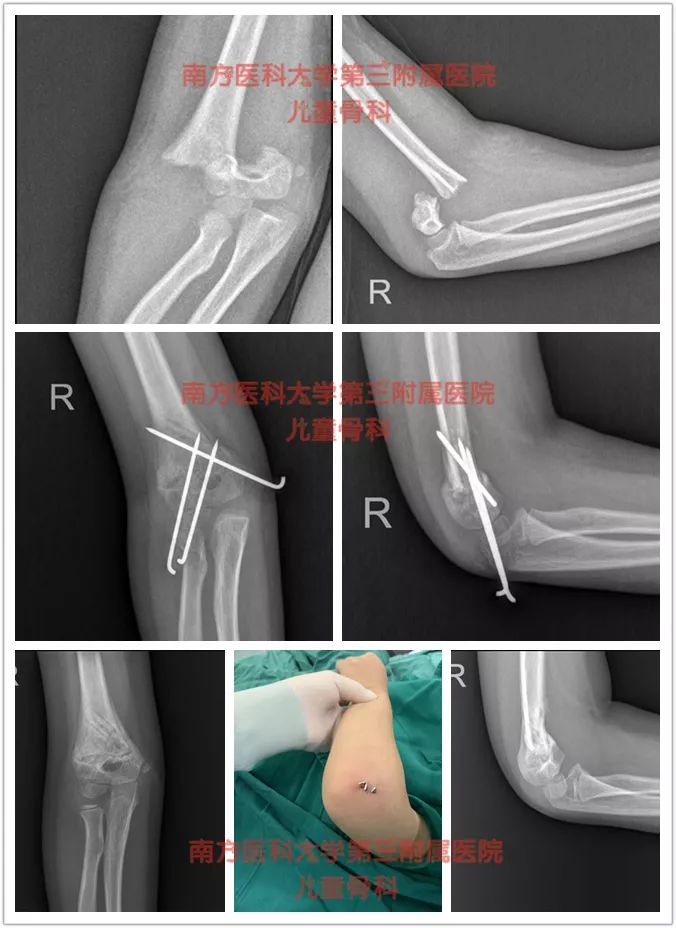

病例1

我科近乎“0”切开几率方式处理肱骨髁上骨折,麻醉下采用手法复位,克氏针交叉固定+石膏固定术,显著的减少了常规保守治疗肱骨髁上骨折高达30%的畸形率。